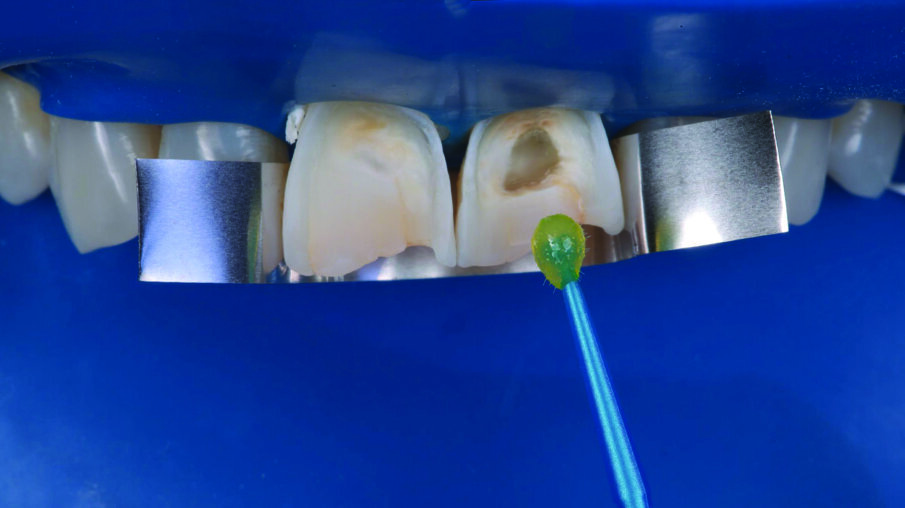

INITIAL SITUATION: Preoperative frontal view of the patient’s teeth, showing severe erosive tooth wear on the vestibular surfaces and incisal edges.

Detailed view of the maxillary incisors. The teeth didn’t show any highly translucent areas, so the use of a single shade/opacity of 3M™ Filtek™ Universal Restorative was selected.

3M™ Scotchbond™ Universal Adhesive was applied to the rinsed and dried tooth structure. The adhesive was rubbed for 20 seconds, treated with a gentle stream of air for solvent evaporation, and light cured for 10 seconds.

Two anterior matrices were placed to help create a natural anterior tooth shape and facilitate restoration of the interproximal and cervical margins.

A 1 mm layer of the Pink Opaquer (PO) was placed onto the discolored sclerotic dentin to mask dark areas and light cured for 20 seconds. The material offered a similar creamy handling as the body shades of 3M™ Filtek™ Universal Restorative.